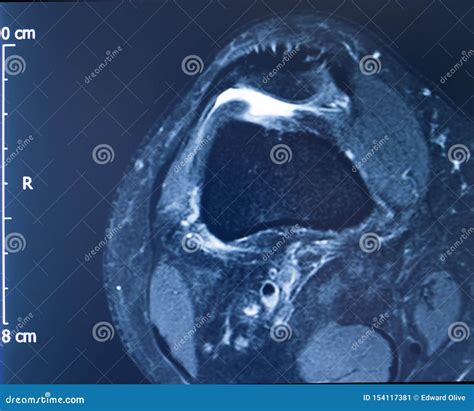

Diagnosing an MCL Tear with an MRI

An Mcl Tear Mri is a non-invasive imaging technique that provides detailed images of the knee joint. MRI uses magnetic fields and radio waves to create cross-sectional images of the body’s internal structures. This allows healthcare professionals to visualize the MCL and other soft tissues in the knee, identifying any tears or damage.

During an *Mcl Tear Mri*, the patient lies on a table that slides into a large, cylindrical machine. The procedure is painless and typically takes about 30-60 minutes. The MRI machine captures multiple images from different angles, providing a comprehensive view of the knee joint.

An *Mcl Tear Mri* is particularly useful for differentiating between an MCL tear and other knee injuries, such as meniscal tears or anterior cruciate ligament (ACL) injuries. This information is crucial for developing an appropriate treatment plan.